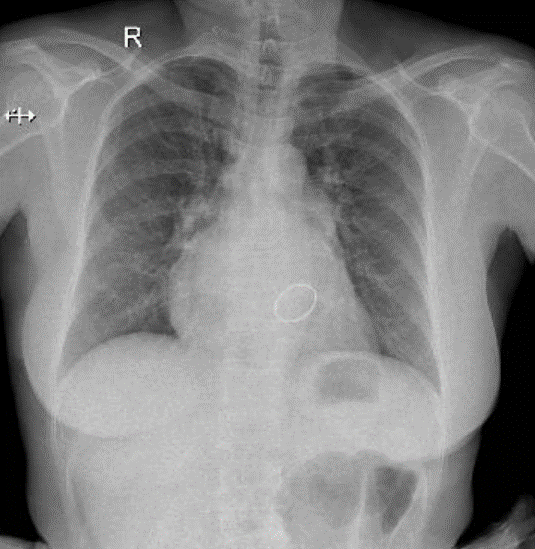

Hãy phân tích tình huống NỮ 50 tuổi -CĐ: Phẫu thuật thay val 2 lá cơ học, lấy huyết khối nhĩ (T), sữa val 3 lá

1-Bóng tim to 2- Val 2 lá nhân tạo